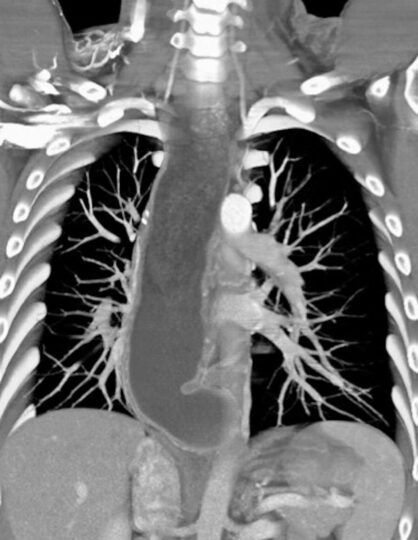

TC DE TORAX .

La Acalasia es un trastorno poco frecuente, que dificulta el paso de alimentos y líquidos hacia el estómago. La acalasia se presenta cuando se dañan los nervios del esófago. En consecuencia, el esófago pierde la capacidad de empujar el alimento hacia abajo, y la válvula muscular que se encuentra entre el esófago y el estómago( esfínter esofágico inferior) no se relaja por completo, lo que dificulta que el alimento llegue al estómago.